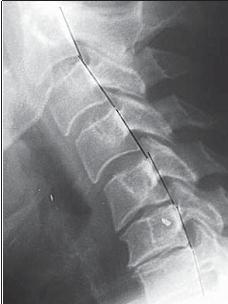

МРТ № 3

На МРТ № 3 — поясничный отдел позвоночника. (На данном «контрольном» снимке наблюдаются остаточные явления дегенеративно-дистрофического процесса в сегменте LV-SI после устранения методом вертеброревитологии секвестрированной грыжи межпозвонкового диска.)

В поясничном отделе форма позвоночного канала, создаваемая телом и дужками позвонка, вариабельна, но чаще она пятиугольная. В норме позвоночный канал в пояснично-крестцовом отделе сужен в переднезаднем диаметре на уровне LIII и LIV позвонков. Его диаметр каудально увеличивается, и поперечное сечение канала приобретает форму, близкую к треугольной, на уровне LV-SI. У женщин канал имеет тенденцию к расширению в нижней части крестцовой области. Сагиттальный диаметр значительно уменьшается от LI к LIII почти неизменен от LIII к LIV и увеличивается от LIV к LV. В норме переднезадний диаметр позвоночного канала в среднем равен 21 мм (15–25 мм).

Существует простая и удобная формула определения ширины позвоночного канала:

нормальный сагиттальный размер не менее 15 мм;

11–15 мм — относительный стеноз;

менее 10 мм — абсолютный стеноз. Уменьшение этого соотношения свидетельствует о сужении канала.

Высота поясничных межпозвонковых дисков 8–12 мм, нарастает от LI до LIV-LV, обычно уменьшается на уровне LV-SI